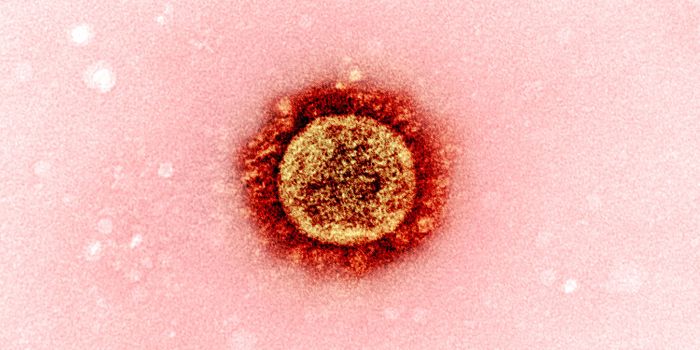

JUL 11, 2021MicrobiologyIn October 2020, what's now called the Delta variant of SARS-CoV-2 was first detected. It's now the most prevalent strai ...

NOV 01, 2021Cell & Molecular BiologyResearchers have learned a lot about the SARS-CoV-2 virus since the start of the COVID-19 pandemic. We know that he viru ...

SEP 07, 2021MicrobiologyThe world has rapidly become familiar with sarbecoviruses, two of which jumped to humans in recent years. The first was ...